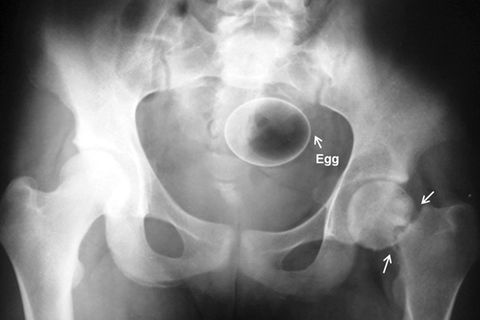

Schildkröte

<blockquote class="twitter-tweet" data-width="540"><p lang="en" dir="ltr">This x-Ray of a pregnant turtle would make a killer album cover <a href="http://t.co/rfsJXhE9je">pic.twitter.com/rfsJXhE9je</a></p>— onagapnotsew (@westonpagano) <a href="https://twitter.com/westonpagano/status/613826375062056960?ref_src=twsrc%5Etfw">June 24, 2015</a></blockquote>